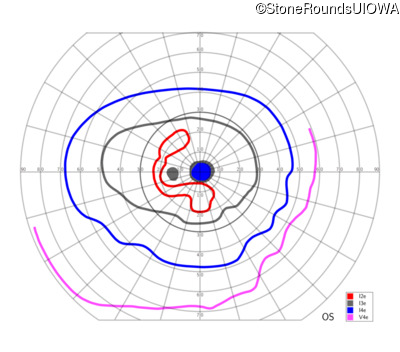

This 52 year old man had normal vision until his mid 30's when he began to have trouble distinguishing colors. the issuing 10 years he had a gradual loss of visual acuity accompanied by increasing photophobia.

| Age at visit: 55 years |

| Age at visit: 58 years |

| Age at visit: 61 years |

| Age at visit: 64 years |